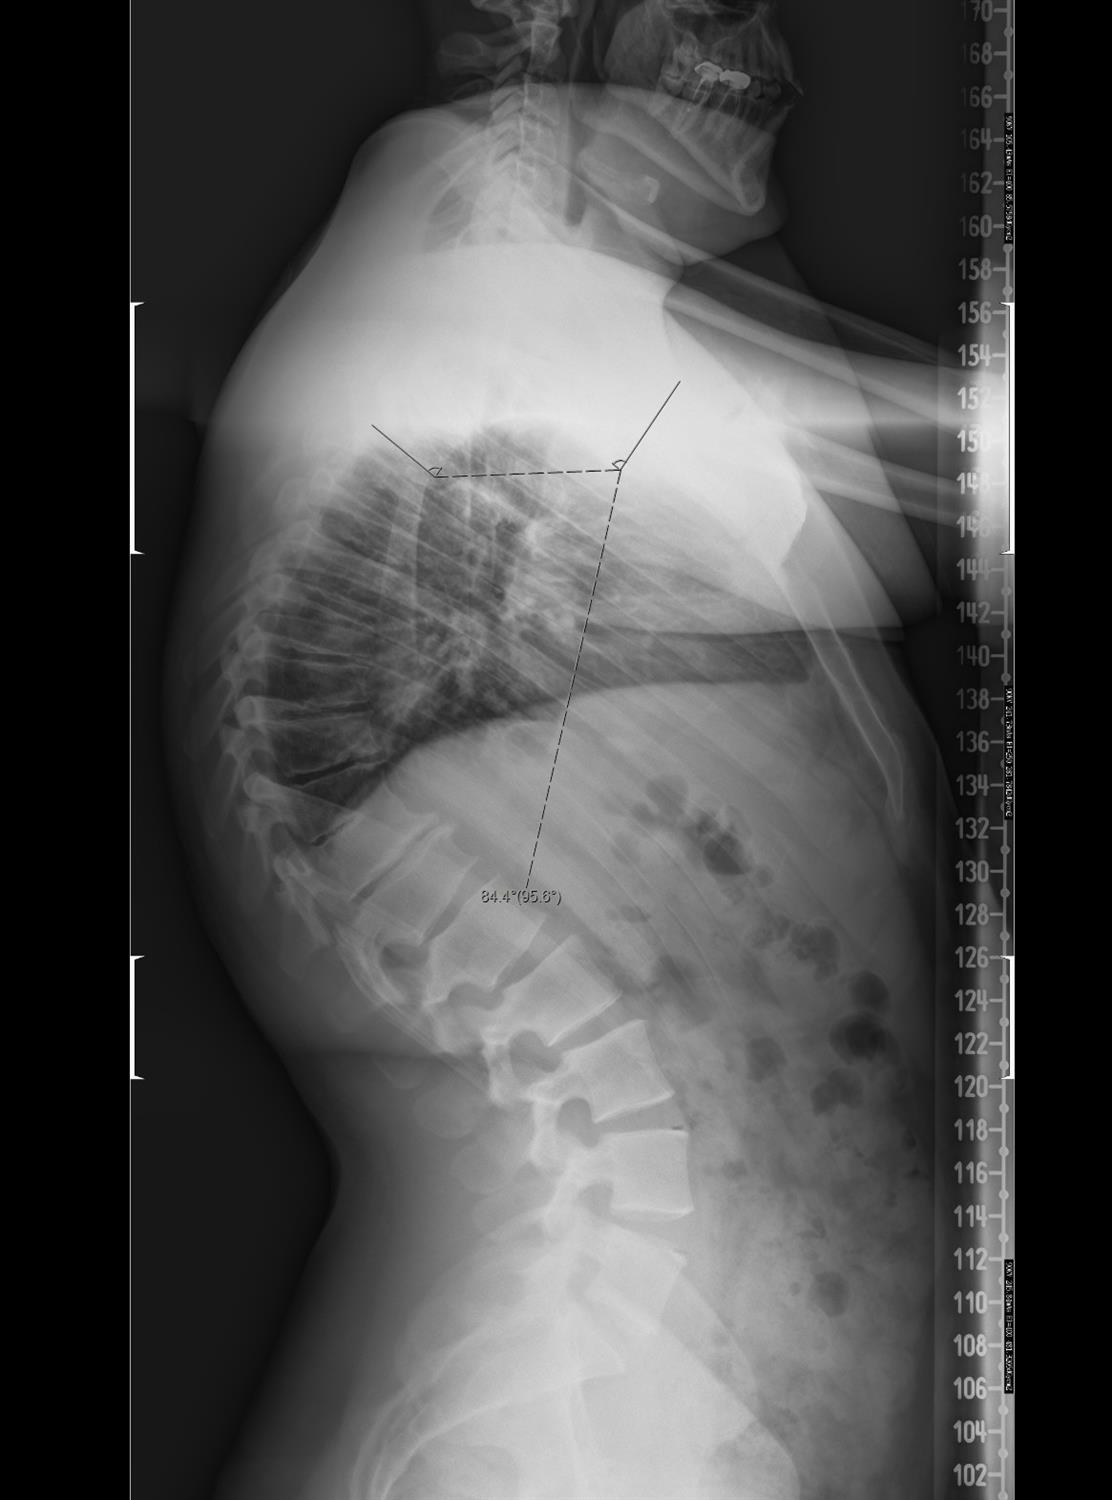

Η ενδελεχής κλινική εξέταση είναι το Α και το Ω στο να τεθεί η υποψία της διάγνωσης. Εντούτοις, ειδικές λήψεις (ακτινογραφίες) της σπονδυλικής στήλης θα αποκαλύψουν το πρόβλημα και θα θέσουν τη διάγνωση. Τα απεικονιστικά ευρήματα στην ακτινογραφία είναι χαρακτηριστικά της νόσου, αλλά χρειάζεται εμπειρία για να διαφορδιαγνωστεί απο τη λειτουργική κύφωση.

Η χειρουργική αντιμετώπιση της κύφωσης τύπου Scheuermann πλέον χρησιμοποιείται πολύ σπάνια και μόνο όταν η σωστή συντηρητική θεραπεία έχει αποτύχει ή όταν ο ασθενής δεν συνεργάζεται με την θεραπεία με τον κηδεμόνα. Σε αυτό έχουν βοηθήσει τα πολύ καλά και μόνιμα διορθωτικά αποτελέσματα με την κατάλληλη συντηρητική θεραπεία (συνδυασμός κηδεμόνα και ειδικών ασκήσεων). Τα άτομα που τελικά οδηγούνται στο χειρουργείο είναι με κυφώσεις άνω των 80 μοιρών και σημαντικό πόνο.